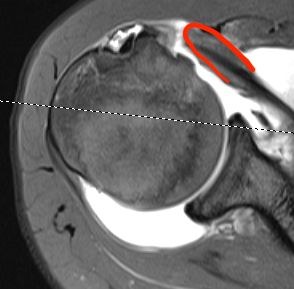

MRI

Patterns

- full thickness retracted tears (comma sign)

Perched long head of biceps with tear of upper border of subscapularis

Full thickness retracted subscapularis tear

Full thickness retracted subscapularis tear with medial dislocation of long head of biceps tendon